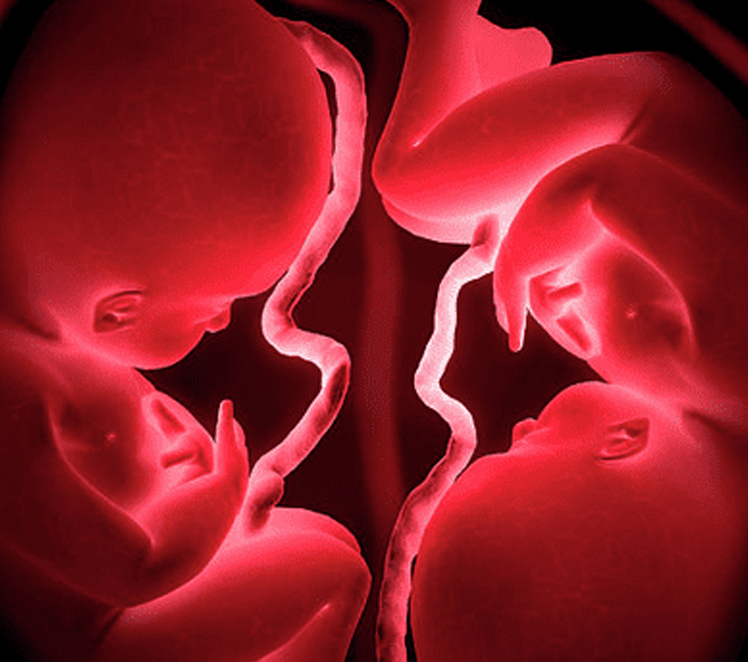

يتميز المركز بتخصصه في متابعه التوائم ولان الحمل في أكثر من جنين يصنف انه حمل خطر ومعرض لكثير من المشاكل الصحية للأجنة كان لزاما علي الام المتابعة الدقيقة لتفادي حدوث مضاعفات او مشاكل للأجنة. وفي حالة حدوث مشاكل صحية يقوم السادة الاستشاريين بمتابعة جيدة وفقا للجايدلاين العالمية .